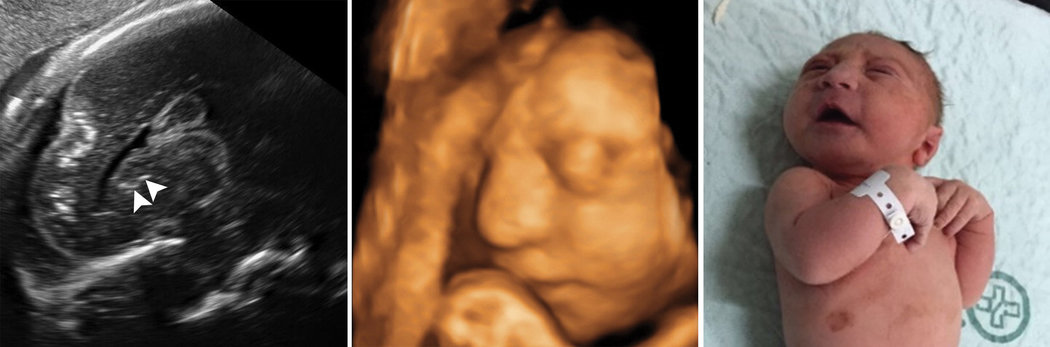

这些图片讲述了一个令人心碎的故事:从大脑内部观察兹卡病毒对婴儿大脑的灾难性损害。

通过一系列令人毛骨悚然的脑部扫描和超声波影像,一项新的研究详细展示了45名巴西婴儿的大脑遭遇的损伤。她们的母亲在怀孕期间曾感染兹卡病毒。周二发表于《放射学》(Radiology)杂志的这项研究,是此类影像收集中最全面的,揭示了一种可以在引发小头畸形之外造成其他损伤的病毒。小头畸形是头异常小的一种症状,已经成为受兹卡病毒侵害的典型特征。

这项研究中的婴儿出生时大多都有小头畸形症,不过他们中有不少也遭受了其他损伤,包括大脑重要部分的损伤:连接两个大脑半球的脑胼胝体;对运动、平衡和速度至关重要的小脑;以及与思维和情绪有关的基底神经节。

这些图像中有一些来自两名双胞胎女孩,她们都有小头畸形症。莱文表示,在两人的脑部图像中可以看到重叠的脑皮层褶皱和倾斜的前额,这表示她们不仅脑部比较小,而且前脑发育不正常。